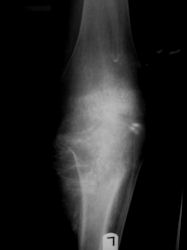

Radiographic imaging is used to help form a diagnosis. These include X-Ray, MRI, CT and Bone Scans

An example of a Conventional Osteosarcoma X-Ray is shown.

Osteosarcoma Diaphyseal